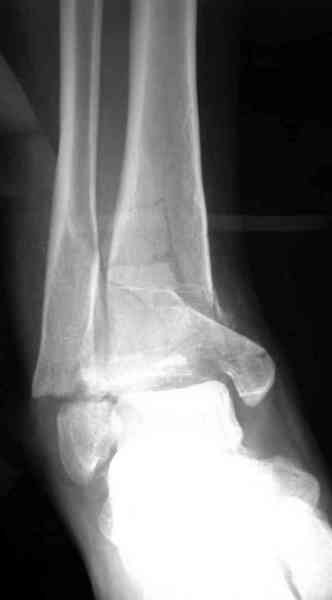

Яков изложил все необходимые аспекты лечения переломов пилона, и, не желая менять тему, решил выставить нашу точку зрения в двух клинических примерах.

При лечении внутрисуставных переломов типа "Pilon"

или "Tibial Plateau" на голени, применение простых

наружных фиксаторов типа "Spanning ExFix" или "Travelling ExFix" стал одним из стандартом этапного лечения.

Здесь выставлена пара случаев перелома пилона, оба

случая леченные этапным наружным фиксатором.